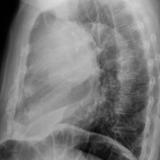

Case 1b

Thymoma